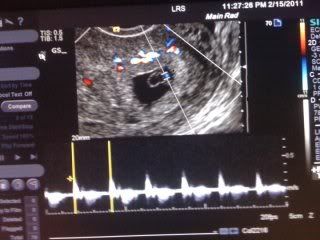

Baby Update (PIP)

Hello ladies! I have been having serious withdrawals the past few

days. I am sure most of you know, my little bambino, is quite the

trouble maker. After not being able to keep down any food/liquid for 7

days and 1 trip to the ER, my OBGYN admitted me into the hospital. I am

still really sick (booo), but at least I am now hydrated. I did get a

early u/s while I was in there, which made me very happy. I am not as

far along as they originally thought, but only about 5 days behind. Here

is a pic, if anyone wants to see. Its kinda blurry because it was taken

with my mom cell phone off the screen. Since it was done in the ER,

they wouldn't give me any printed pics. ![]() Anyway, the heart beat was

132, which the nurse said was good. This picture shows the heart beat at

the bottom, and then the blue spot inside the sac, is the baby's heart

beating.

Anyway, the heart beat was

132, which the nurse said was good. This picture shows the heart beat at

the bottom, and then the blue spot inside the sac, is the baby's heart

beating.